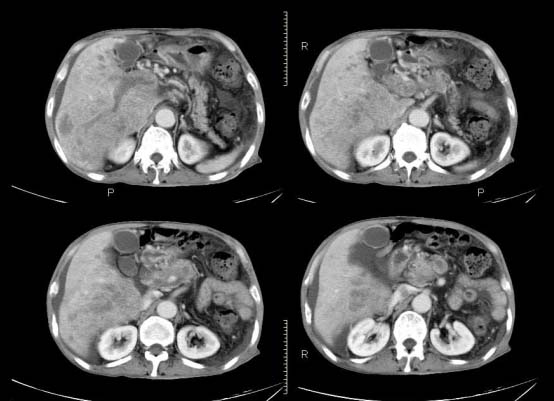

以下是引用杀毒软件在2010-3-30 18:11:00的发言:[br]考虑---hcc侵犯侵犯周围组织〔胰腺、胆管、肠系膜上动静脉〕伴门脉、下腔静脉癌栓形成、动-静脉瘘、肝门、腹腔动脉周围淋巴结转移可能性大、腹水。

以下是引用pujunzhi在2010-3-31 8:45:00的发言:[br]支持 肝癌并多发肝内转移,胰头、肝门、腹腔动脉周围淋巴结转移,下腔静脉癌栓形成,肝硬化、腹水。

以下是引用jsgdoctor在2010-3-30 20:42:00的发言:[br]考虑---hcc侵犯侵犯周围组织〔胰腺、胆管、肠系膜上动静脉〕伴门脉、下腔静脉癌栓形成、动-静脉瘘、肝门、腹腔动脉周围淋巴结转移可能性大、腹水。